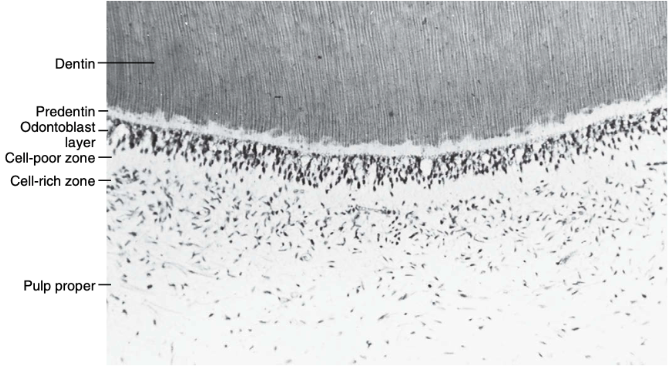

morphologic zones of the pulp

pulp-dentin complex

odontoblast layer

cell-poor zone

cell-rich zone

pulp proper

aka: cell-free zone / zone of Weil

sensory transmission, lies beneath the odontoblastic layer

cell-poor zone contains:

few cells, many nerves

blood capillaries plexus

cytoplasmic processes of fibroblasts

unmyelinated nerve fibers (Raschkow’s plexus)

approximate width of cell-poor zone

40 μm

found beneath the cell-poor zone

aka: pulp core / central pulp

the central mass of the pulp